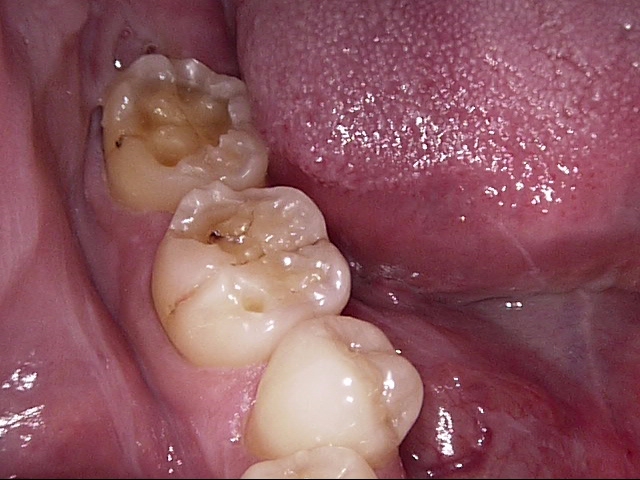

PEEK冠の1例↓

現状の保険診療での大きな奥歯に被せ物に関しては、耐久性だけでいいますと通常の銀歯が一番あるかと思います。